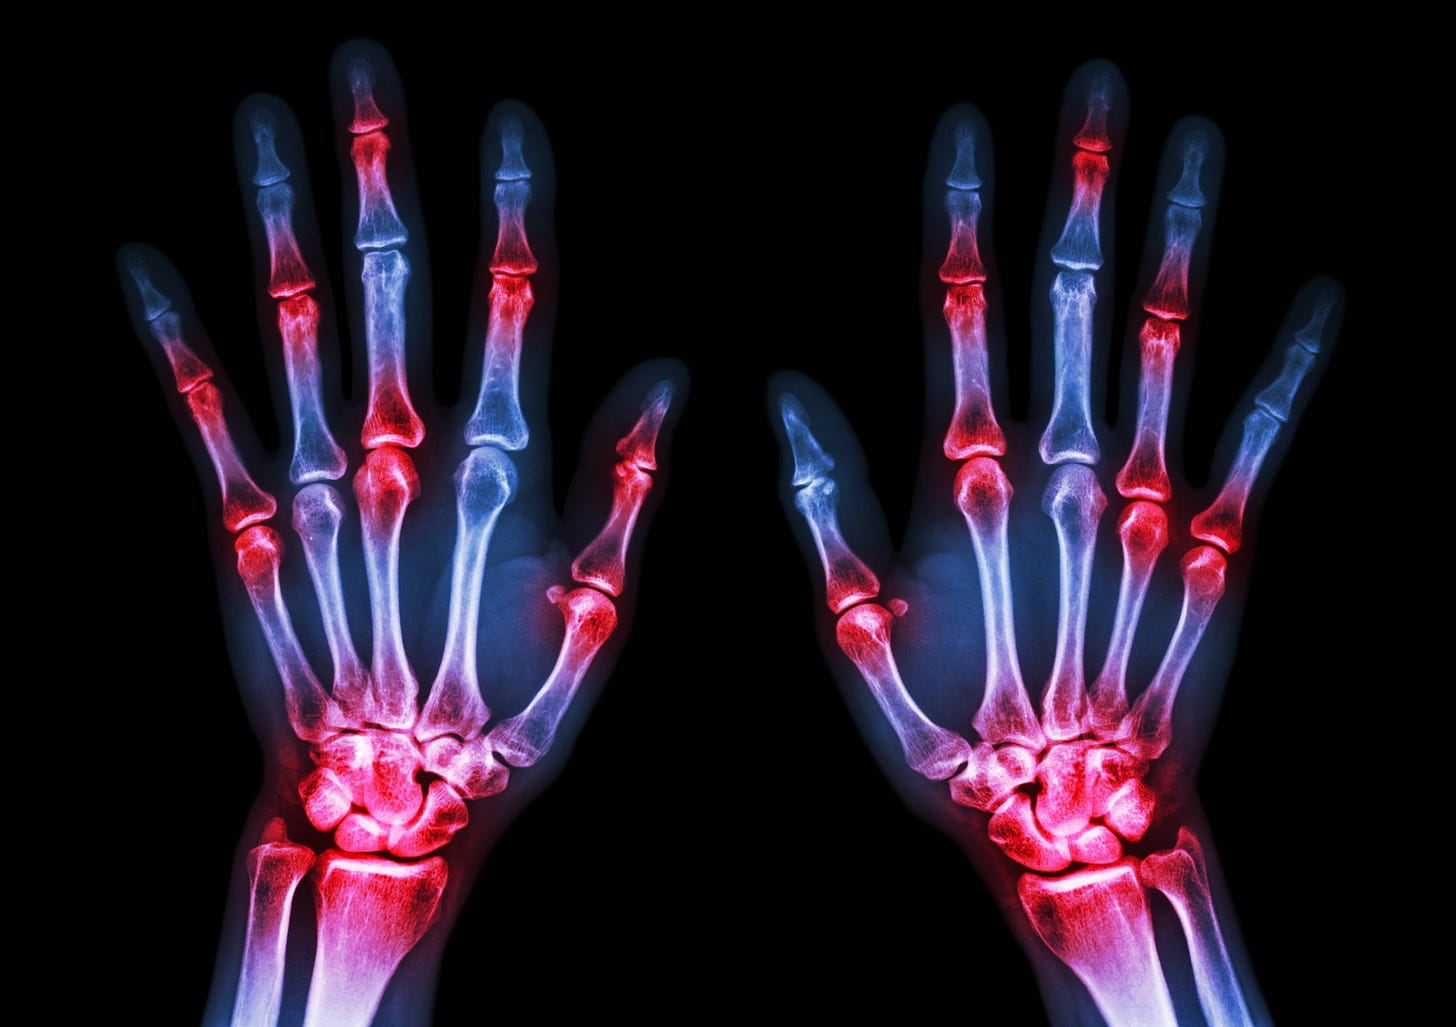

Between 1.3 and 1.5 million Americans suffer from Rheumatoid arthritis (RA). This autoimmune condition can be debilitating on a regular basis to those who suffer flares and progression; it is can also lower a person's life expectancy by as many as ten to fifteen years.

In people with RA, citrullinated peptides are generated through a process called citrullination. Citrullination is a post-translational modification of proteins, where the amino acid arginine is converted into citrulline by an enzyme called peptidyl arginine deiminase (PAD). This modification can alter the structure and function of proteins, leading to changes in their antigenic properties.

Dysregulated Immune Response: In individuals with a genetic predisposition to RA, exposure to environmental triggers can lead to an inappropriate immune response. Immune cells may recognize citrullinated peptides as foreign or abnormal, leading to the production of ACPAs and the activation of autoimmune processes. The resulting chronic inflammation and immune-mediated tissue damage are hallmarks of RA.

Role of PAD Enzymes: The peptidyl arginine deiminase (PAD) enzymes are critical for the citrullination process. There are several PAD isoforms, with PAD2 and PAD4 being the most relevant to RA. These enzymes are expressed in various tissues, including the synovial joints affected in RA. Elevated PAD activity in the synovial fluid has been observed in RA patients, contributing to the citrullination of proteins in the inflamed joints.